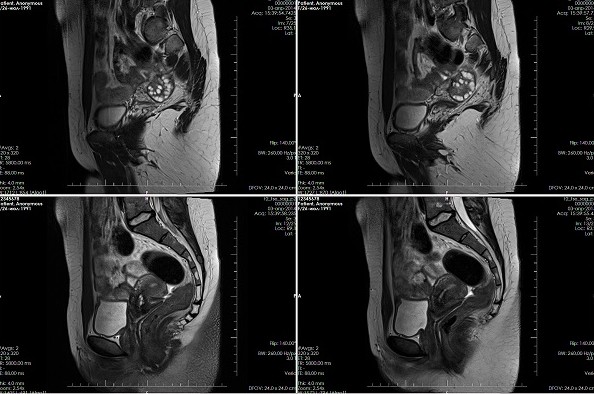

МРТ малого тазаТочности магнитно-резонансной томографии достаточно, чтобы увидеть малейшие изменения в органах и тканях. Толщина среза не превышает 1 мм, что позволяет достоверно выявлять воспалительные процессы, новообразования, кисты, патологии сосудов и иные нарушения, встречающиеся в хирургии, гинекологии, андрологии, урологии, онкологии.

МРТ малого таза: расшифровка результатовРезультатом МРТ малого таза становится серия снимков, полученных посредством обработки данных специальными компьютерными программами. Изображения изучаются специалистом в области лучевой диагностики, который фиксирует все отклонения от физиологической нормы и описывает выявленные патологии. В сложных случаях, если расшифровать снимки МРТ малого таза не представляется возможным, привлекаются врачи узкого профиля, в том числе зарубежные диагносты. Делается это с помощью современных телекоммуникационных технологий.